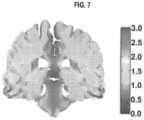

- FIG. 7 illustrates electric field magnitude and distribution (in V/cm) shown in the coronal view from a finite element method simulation model. This simulation employs a left-right paired transducer array configuration.

- the results of these simulations employing paired array configurations, a constant current, and a preset frequency of 200 kHz, have demonstrated that electric field distributions are relatively non-uniform throughout the brain and that electric field intensities exceeding 1 V/cm are generated in most tissue compartments except CSF. These results are obtained assuming total currents with a peak-to-peak value of 1800 milliamperes (mA) at the transducer array-scalp interface.